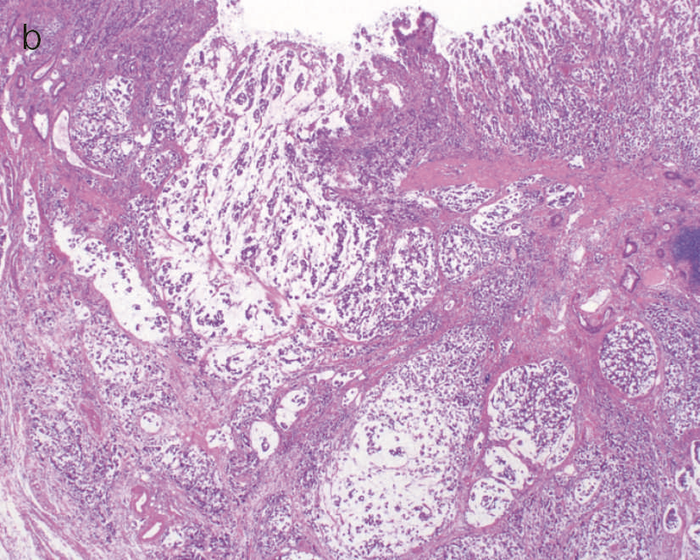

2)病理診断

- UC関連進行大腸癌の肉眼像は潰瘍浸潤型(3型),びまん浸潤型(4型)や分類不能型(5型)が多い。同初期病変の多くは隆起型,平坦型,あるいはその混合型であり,平坦型成分はdysplasiaの特徴といえる。

- 肉眼的特徴

通常の散発性進行大腸癌の多くは潰瘍限局型(2型)であるが,UC関連進行大腸癌は潰瘍浸潤型(3型),びまん浸潤型(4型)や分類不能型(5型)が多いとされる(図7)。初期病変であるdysplasiaの肉眼形態に関しては,混合型を含む約70%の症例が何らかの隆起成分を有することが報告されている1,2)。ただ同じ隆起といっても,UC関連大腸腫瘍の多くは境界不明瞭な丈の低い顆粒状・結節状・不整扁平隆起を呈する一方で,散発性腫瘍は有茎性もしくは亜有茎性病変,境界や立ち上がりが明瞭な病変であることが多く,詳細な肉眼形態の観察は両者の鑑別に重要である。二番目に多い肉眼形態は平坦型であり,全体の約30%を占める1,2)。散発性大腸腫瘍の平坦型は極めて頻度が低いことから,平坦型成分の存在もdysplasiaの特徴といえる(図8)。

図8 Dysplasiaの代表的な肉眼像(平坦型)

- 直腸部の赤色点線部より肛門側(左側)に拡がるdysplasia(平坦型)を認める。

- 同平坦部では組織学的に高分化管状腺癌(粘膜内癌)を認めた。